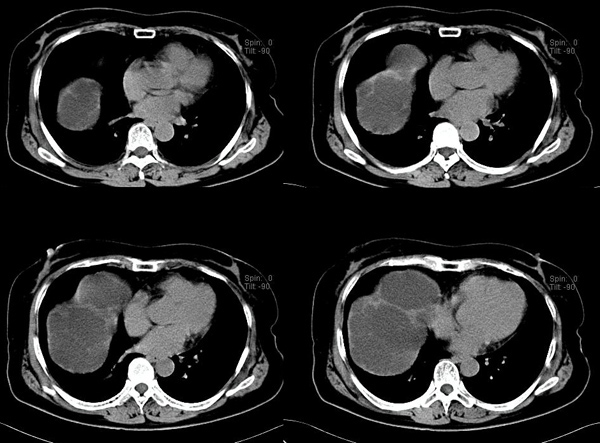

美国约有2%的人口患有胰腺囊肿,其中一部分需要手术切除并进行病理分析,以判断其是否有恶变倾向。胰腺囊肿在中老年人群中较为常见,大多数并不产生临床症状,因此大多数患者对其囊肿并不知晓。但随着MRI、CT、腹部超声等影像学检查的普及,很多胰腺囊肿被发现。而以现有技术,除非手术切除并进行病理分析,否则无法知晓囊肿对患者是否有危害,这使得医生和患者陷入两难的境地。

研究者分别对导管内乳头状瘤(IPMN)、浆液性囊腺瘤(SCA),粘液性囊肿(MCN)和假乳头状实体瘤(SPN)进行了研究。结果发现每一类型的囊肿都有其特异性的基因改变:SCA的3号染色体片段丢失,破坏了抑癌基因VHL的活性;MCN的生长驱动癌基因KRAS突变,以及抑癌基因RFN43基因突变或丢失;而SPN仅有CTNNB1基因突变,该基因在肿瘤发生中的作用尚不明确,多数肿瘤仅在多次突变后才会出现;IPMN的癌基因KRAS和GNAS突变,也有RFN43突变。